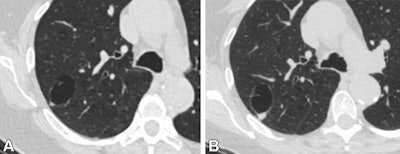

CT images in a 74-year-old female patient. (A) Axial image from a lung cancer screening shows a 3.1 cm by 2 cm unilocular cystic lesion with a 0.5 cm solid nodular component in the right upper lobe. The overall size of the lesion and solid nodular component ultimately grew. (B) Follow-up CT image obtained 37 months later, before resection, shows a 3.5 cm by 2.4-cm lesion with a 0.8-cm solid component. This lesion was pathologically proven to be invasive adenocarcinoma. Images and caption courtesy of the RSNA.CT images in a 74-year-old female patient. (A) Axial image from a lung cancer screening shows a 3.1 cm by 2 cm unilocular cystic lesion with a 0.5 cm solid nodular component in the right upper lobe. The overall size of the lesion and solid nodular component ultimately grew. (B) Follow-up CT image obtained 37 months later, before resection, shows a 3.5 cm by 2.4-cm lesion with a 0.8-cm solid component. This lesion was pathologically proven to be invasive adenocarcinoma. Images and caption courtesy of the RSNA.